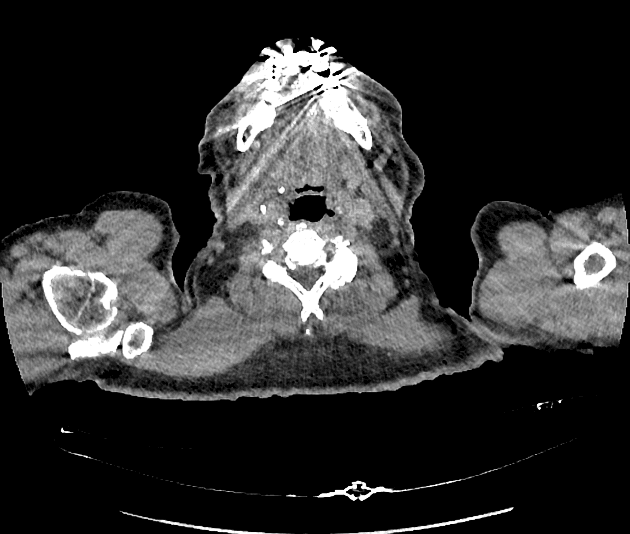

Axial Gradient Echo

- Có các ổ dịch ngấm thuốc viền (peripherally enhancing collections) xung quanh khớp cùng đòn mỏm cùng phải.

- Các ổ này đi kèm với tín hiệu bất thường ở tủy xương trong mỏm cùng (acromion) và đầu xương đòn (distal clavicle), cùng với các ổ ăn mòn vỏ xương (cortical erosions) ở xương đòn.

- Ngoài ra, thấy nhiều ổ dịch ngấm thuốc viền kích thước khác nhau nằm trong mô dưới da và các mặt phẳng cơ.

- Các ổ này lan vào các cơ thang (trapezius), cơ delta (deltoid) và cơ ngực lớn (pectoralis), đi kèm tín hiệu bất thường và ngấm thuốc thì tĩnh mạch cửa (post-contrast enhancement) ở các cơ lân cận và mô dưới da phía trên.

- Trong trường hợp này, sự hiện diện của các ổ dịch ngấm thuốc viền tập trung quanh khớp cùng đòn mỏm cùng, kết hợp với bất thường tín hiệu tủy xương và các ổ ăn mòn vỏ xương ở xương đòn và mỏm cùng, hỗ trợ chẩn đoán viêm khớp nhiễm trùng. Viêm tủy xương kèm theo (osteomyelitis) cũng là một khả năng rất cao.

- Các ổ dịch lan rộng trong cơ và dưới da, ảnh hưởng đến các cơ thang, cơ delta và cơ ngực lớn, biểu hiện cho sự lan rộng của nhiễm trùng với sự hình thành nhiều ổ áp xe – đây là một biến chứng đã được ghi nhận trong nhiễm trùng kéo dài hoặc tiến triển nhanh.

- Đã thực hiện dẫn lưu ổ dịch dưới hướng dẫn hình ảnh, thu được khoảng 400 mL dịch mủ, xác nhận bản chất nhiễm trùng của tổn thương.